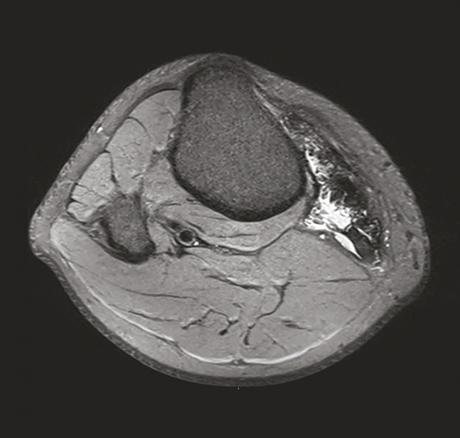

Ce jeune homme de 20 ans consultait pour une douleur du genou évoluant depuis 1 an initialement étiquetée bursite. Un traitement médical lui avait été prescrit pour cette affection. Devant la persistance de la douleur, une échographie était réalisée qui montrait une formation kystique atypique car mal limitée, à paroi épaissie et hyperhémique. Le caractère particulier de cette lésion amenait à prescrire une imagerie par résonance magnétique (IRM) qui montrait une infiltration évoquant une synovite villonodulaire en regard de l’insertion des muscles de la patte d’oie (fig. 1 et 2 ). La lésion était réséquée chirurgicalement et l’examen anatomopathologique notait une prolifération de cellules mononucléées ovoïdes ou comportant des inflexions fusiformes, associées à des histiocytes spumeux et du pigment hémosidérinique, sans atypie cytononucléaire ni activité mitotique, confirmant le diagnostic.